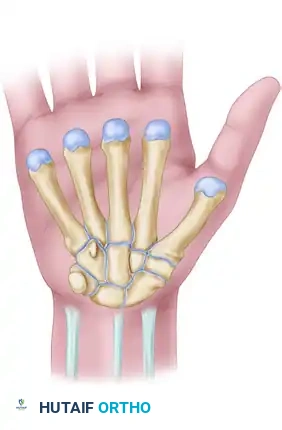

Surgical Anatomy of the Carpal Tunnel

A profound understanding of the flexor retinaculum and its surrounding neurovascular structures is paramount for safe surgical execution. The classic flexor retinaculum is a complex, tripartite structure.

The proximal limit of the retinaculum aligns with the distal aspect of the pisiform, while the distal limit extends just beyond the hook of the hamate.

Anatomically, the flexor retinaculum consists of three distinct portions:

1. Proximal Portion: Deep fascia of the forearm that courses deep to the flexor carpi ulnaris and flexor carpi radialis.

2. Middle Portion (Transverse Carpal Ligament): The thick aponeurosis spanning between the thenar and hypothenar eminences. It attaches radially to the scaphoid tubercle and the trapezium ridge, and ulnarly to the pisiform and the hook of the hamate.

3. Distal Portion: An aponeurotic extension between the thenar and hypothenar musculature.

The median nerve lies superficial to the nine flexor tendons within the canal. The recurrent motor branch of the median nerve exhibits variable anatomy (extraligamentous, subligamentous, or transligamentous) and must be meticulously protected during the distal aspect of the release.

Surgical Techniques: Carpal Tunnel Release

Whether utilizing a standard open approach, a limited-incision technique, or an endoscopic method, the fundamental objective remains identical: complete division of the transverse carpal ligament under direct or endoscopic visualization.